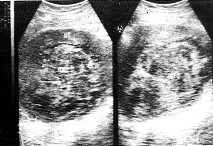

子宫肌瘤变性的声像图特点:(1)玻璃样变:病变切面失去旋涡状结构变为同质、其回声较为衰减(图1)。本组有3例占1.84%;(2)红色变性:为一种特殊型肌瘤坏死,常发生于较大的肌瘤中,妊娠期或产褥期易发生此种变性,切面呈肉红色、保持旋涡状外形,声像图上肿瘤明显衰减,界限不清(图2)。本组有5例占3.06%;(3)囊性变:当玻璃样变继续发展、液化形成许多大小不等的空腔,也可融合成一大囊腔,囊腔内壁光滑、囊内含液体多无色透明。前者有时很像葡萄胎,后者酷似卵巢囊肿,仔细观察瘤体的非囊区仍可见肌瘤的特点,回声较强,亦可以很弱或杂乱(图3,4)。本组有4例,占2.45%;(4)钙化:多发生于玻璃样变坏死后、由于肌瘤血液循环障碍、钙盐被组织成分及其他变性物质所吸收而沉积,超声图像显示为增强的回声团其后伴声影。本组有3例占1.84%。

图1 子宫肌壁间平滑肌瘤伴玻璃样变(手术病理证实)

UT:子宫,MYO:肌瘤 UT:子宫,MYO:肌瘤